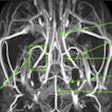

New MRI contrast agent enables 3D vascular mapping